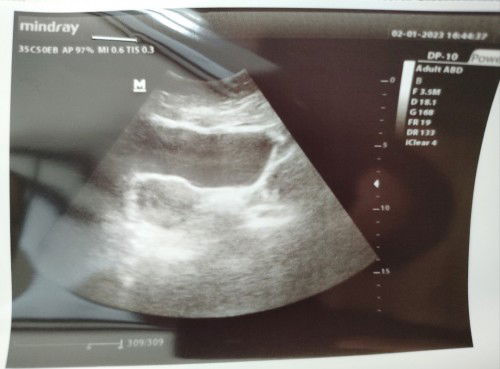

Hai bun.. mau tanya apakah ada yang seperti saya? Saya dihitungkan bidan dengan siklus haid normal, tidak pernah telat.. umur janin di 6 minggu. Tapi kemarin, karena saya ada sedikit flek, saya periksa ke dokter SpOg.. dan ternyata umur janin 3 minggu dan saya diberi penguat kandungan. Apakah itu tidak apa2? Karena saya disuruh periksa lagi minggu depan.. bantu infonya untuk yang pernah mengalami bun.. karena ini pengalaman pertama hamil. Terima kasih. #seriusnanya #ingintahu #firstmom #pleasehelp